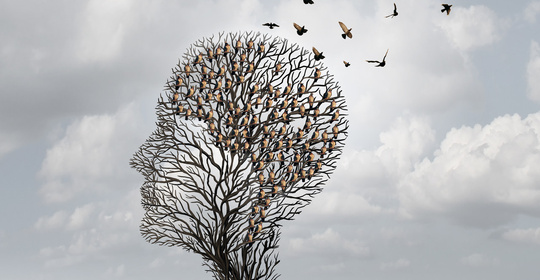

智力發育遲緩:兒童發育小知識,教育與關愛方法!

語言發育遲緩:兒童發育小知識,教育與關愛方法!